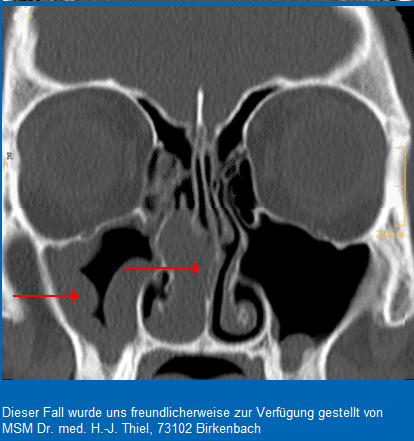

Ülalõuaurkepõletik

Sinuiiti diagnoositakse ülemiste hingamisteede sümptomitega täiskasvanuil ja üle4-aastastel lastel ultraheli abil. – Antibiootikumi määratakse ainult neile patsientidele, kellel on leitud ülalõuaurkes eritist. – Sinuiit on astmahaige seisundi halvenemise põhjus. – Korduvate … Loe edasi »